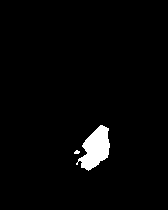

In this way, we are able to obtain a normal version of the given pathological image. In order to obtain an anomaly map, we first compute the difference between the original and the generated image and then apply erosion followed by dilation with a kernel to the resulting map, in order to remove noise, and finally dilation followed by erosion, with the same kernel, to close small holes in the map.